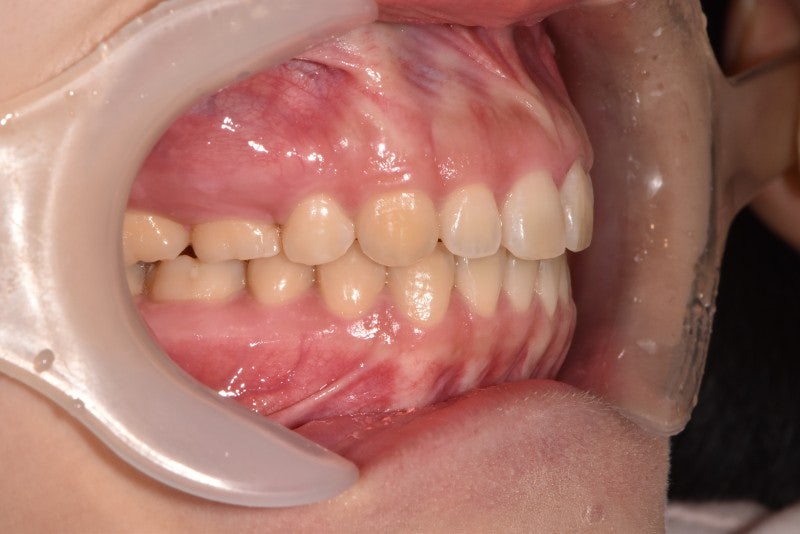

-비수술적 안면비대칭교정 사례-사례1(일측성 비대칭 상악연전)